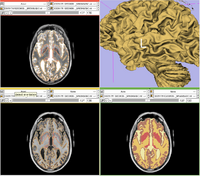

Automatic segmentation can be performed reliably using priors from brain atlases and an image generative model. We have developed a tool that provides an automatic segmentation pipeline in a modular framework. The processing pipeline is composed tasks such as filtering the input images, registering the multimodal input images and the brain atlas to a common space, followed by iterative steps which interleave segmentation, inhomogeneity correction, and atlas warping.

Our tool generates bias corrected images, fuzzy classification maps, and discrete segmentation labels. The tool has been used to automatically segment thousands of adult and toddler images from the University of North Carolina (UNC), and is also being used as a skull stripping mechanism for DTI processing at UNC and Utah. An example of the output of the tool is shown below.

The tool has been integrated into Slicer as an extension, and it can also be executed as a stand-alone application. Both versions are available for download through NITRC: http://www.nitrc.org/projects/abc .

Screen shot of the segmentation plugin in Slicer.

Screen shot of the stand-alone segmentation GUI.